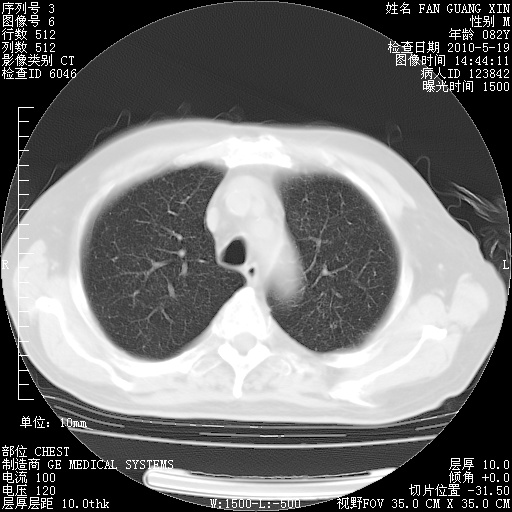

复查肺部CT,明显好转。为什么发热呢?

治疗3周后的肺部CT

治疗3周后的肺部CT纵隔窗